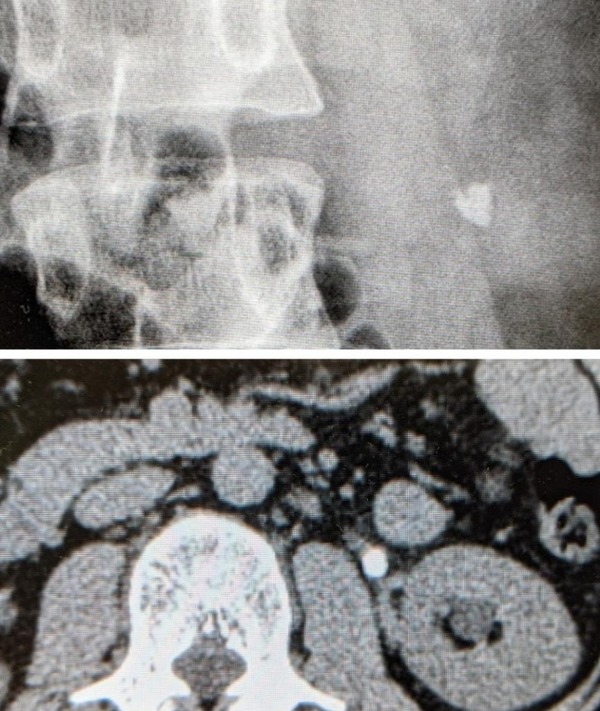

51: 風吹けば名無し 2022/04/29(金) 08:18:04.93 ID:GBRid4Aa0

ワイのな

もう出したで

53: 風吹けば名無し 2022/04/29(金) 08:20:19.09 ID:5VUB2+/10

>>51

すごいおにぎり。ワイのは普通に米粒型だったな